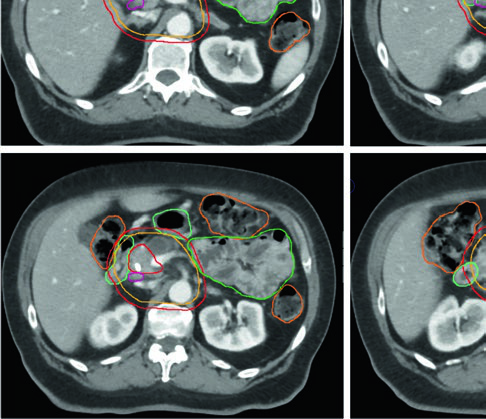

Volúmenes blanco en el escenario definitivo

| Volumen | Definición y descripción |

|---|---|

| GTV | Toda enfermedad macroscópica en imagen, incluyendo el tumor primario y la extensión vascular |

| ITV (opcional) | Si se utiliza enfoque ITV, delinear el GTV en todas las fases del 4D-CT |

| CTV alta dosis | Corresponde al GTV (o ITV si se utiliza) sin margen adicional |

| CTV dosis microscópica | Expansión uniforme ≥ 1 cm sobre toda la enfermedad macroscópica + cadenas CA y AMS + hilio esplénico (cuerpo/cola) + margen vascular adicional + porta hepatis opcional (cabeza) |

| PTV alta dosis | Expansión 0–0,5 cm, sustrayendo OARs críticos superpuestos con margen de seguridad: • 56 Gy/28 fx o 33 Gy/5 fx: sustraer estómago e intestino delgado sin margen adicional • 50 Gy/10 fx, 67,5 Gy/15 fx o 75 Gy/25 fx: sustraer con expansión de 0,5 cm (0,7 cm para interfaz larga) |

| PTV microscópico | Mínimo 0,5 cm; sin ITV en respiración libre, 1–1,5 cm craneocaudal |

Fuente: Target Volume Delineation and Field Setup, 2nd Edition (Table 16.2)

Un detalle práctico que a menudo se subestima: dada la naturaleza infiltrativa del PDAC, el sobre-contorneo del GTV para incluir el parénquima pancreático circundante puede ser razonable, especialmente cuando se respalda con imagen diagnóstica adicional. En regiones de contacto directo entre GTV y OAR crítico, el PTV debe excluir el OAR con un margen de seguridad que exceda la expansión del PRV.